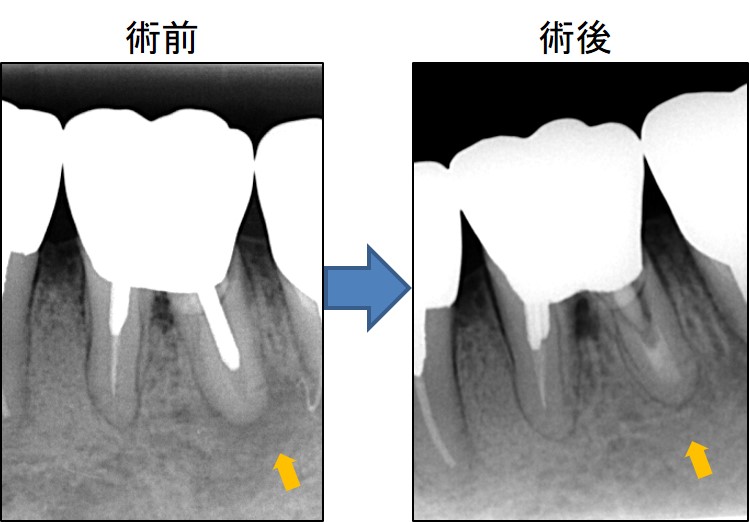

下写真は左が術前、右が術後です。

術前写真のオレンジ矢印部分に黒い影があります。根管の中が細菌感染しているため膿んでいます。

術後は黒い影が無くなり、骨が再生しています。